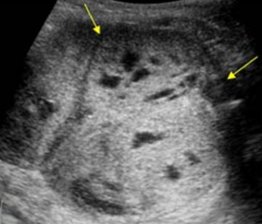

- УЗИ органов брюшной полости и забрюшинного пространства — выявление опухоли в трех измерениях и определение объема опухоли. При УЗИ может быть визуализирован опухолевый тромб в нижней полой вене.

Рисунок 2. КТ: опухоль при поступлении. Клинически: при пальпации опухоль в проекции правой почки до 12 см в диаметре. Общеклинические исследования в пределах возрастной нормы. При КТ органов брюшной и грудной полости: КТ-картина объемного образования правой почки без признаков интрапульмональных метастазов (см. рис. 2). УЗИ брюшной полости: в проекции правой почки солидно-кистозное образование 101ґ114ґ99 мм, объемом 500 мл, васкуляризация активная, интактная часть почки 57ґ12ґ40 мм. Объемное образование правой почки — опухоль Вильмса. Предварительный диагноз: опухоль Вильмса правой почки, 2-я стадия.